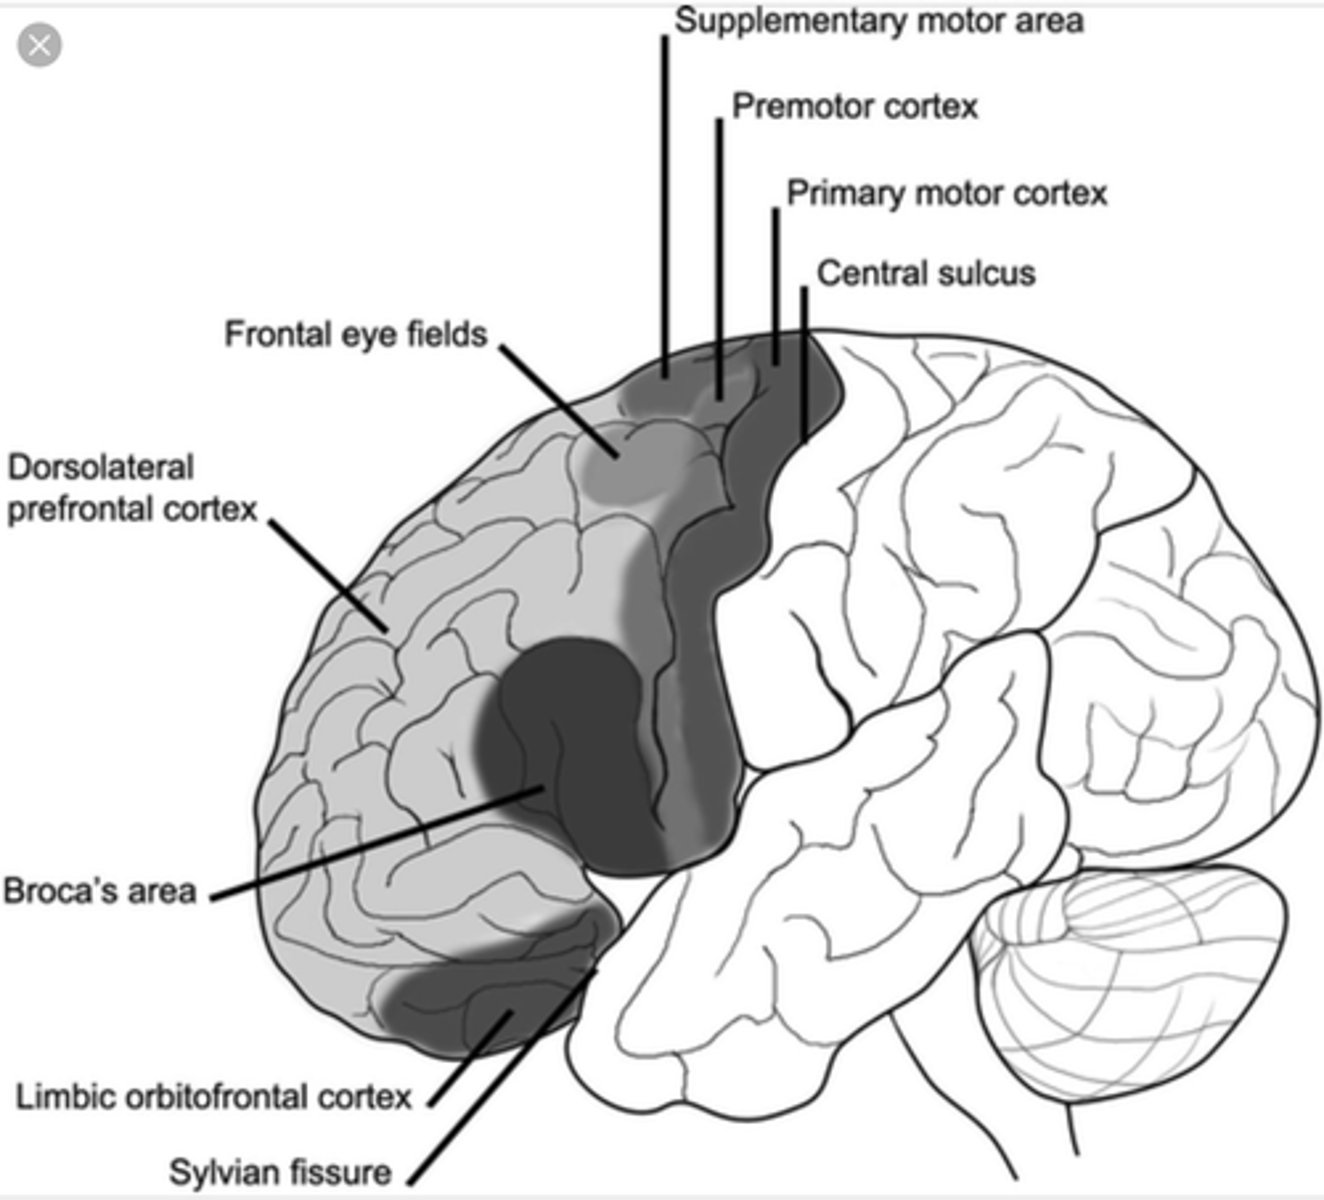

What is efferent to the lateral portion of the medial nucleus of the thalamus?

frontal eye fields (anterior cortex of the frontal lobes)

why? -- control eye movements

What are the functions of the lateral portion of the medial nucleus of the thalamus?

1. control eye movements and attending to visual stimuli

2. role in emotional "tone"

What is efferent to the medial portion of the medial nucleus of the thalamus?

1. limbic areas (emotion)

2. insular cortex

3. orbital frontal cortex

What are the functions of the medial portion of the medial nucleus of the thalamus?

1. autonomic regulation

2. emotions

why the GI can act up from emotions